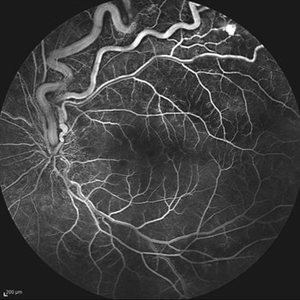

Behcet's Disease Behcet's DiseaseMar 13 2013 by Hamid Ahmadieh, MD Early phase FA of the right eye of a 23-year-old man with retinal vasculitis and branch retinal vein occlusion (BRVO) due to Behcet's disease . Photographer: Solmaz Shahmohammad, Negah Eye Center, Tehran Imaging device: Heidelberg Spectralis Condition/keywords: branch retinal vein occlusion (BRVO), retinal vasculitis

Behcet's Disease Behcet's DiseaseMar 13 2013 by Hamid Ahmadieh, MD Mid phase FA of the right eye of a 23-year-old man with retinal vasculitis and branch retinal vein occlusion (BRVO) due to Behcet's disease . Photographer: Solmaz Shahmohammad, Negah Eye Center, Tehran Imaging device: Heidelberg Spectralis Condition/keywords: branch retinal vein occlusion (BRVO), retinal vasculitis